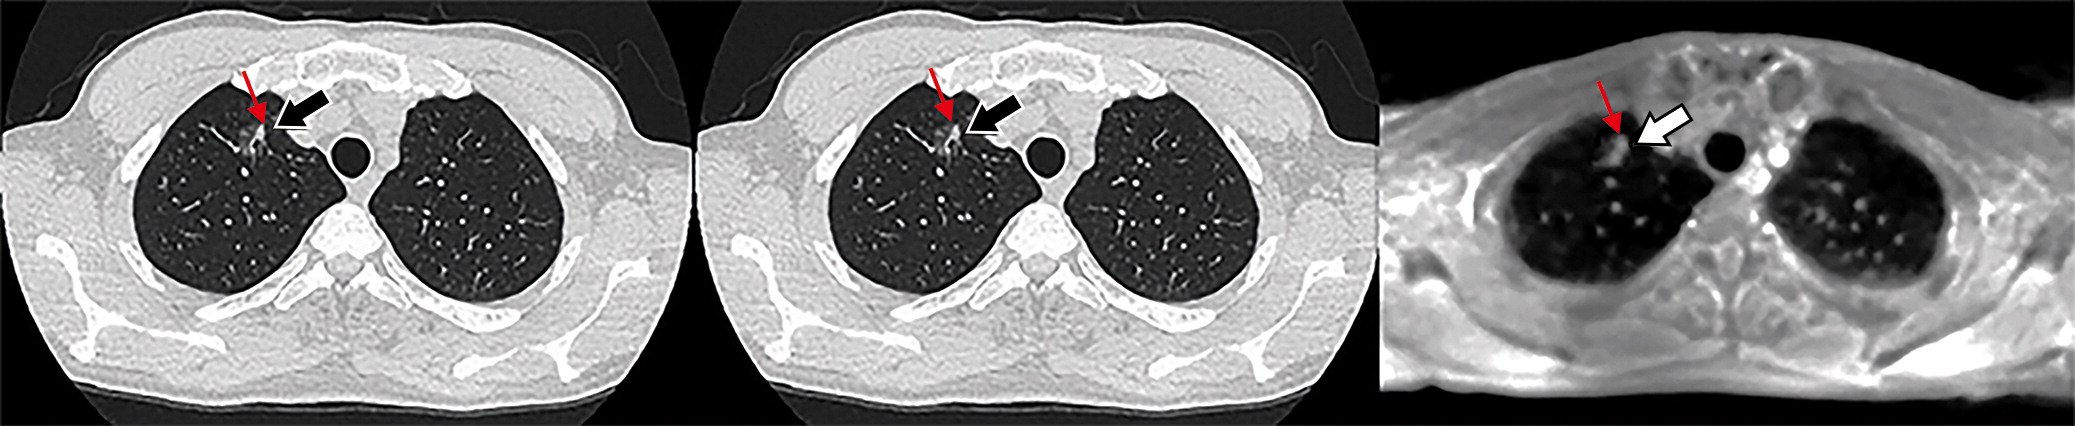

下图展示了一个63岁男性的三种肺部影像。该结节如箭头所指,被诊断为毛玻璃结节;Lung-RADS分类为2类。

b11417871848d2daea9a6bb00003b9e8.jpg